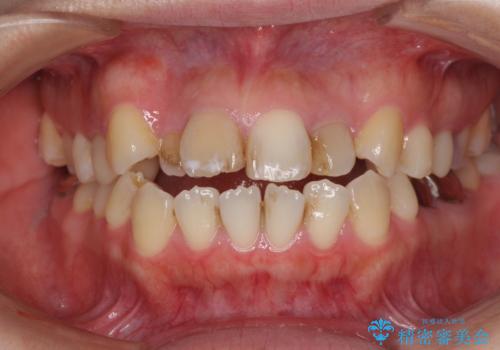

前歯の出っ歯と口の閉じにくさが気になる 目立たないワイヤー装置での抜歯矯正

担当医 藤巻太一朗